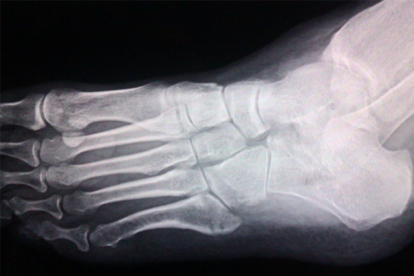

足部撞擊或扭傷可能導(dǎo)致跖骨骨折、韌帶損傷。急性期會出現(xiàn)局部淤血和壓痛。需通過X線明確損傷程度,輕微骨裂可用支具固定,完全骨折需手術(shù)復(fù)位。傷后48小時內(nèi)冰敷,后期配合紅外線理療促進恢復(fù)。